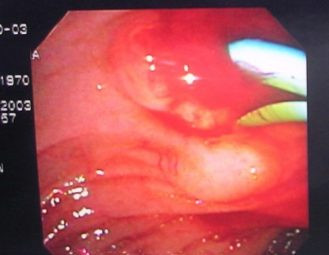

Colagiopancreatografía Retrógrada Endoscópica (ERCP)

Envíado por Gastroclínica